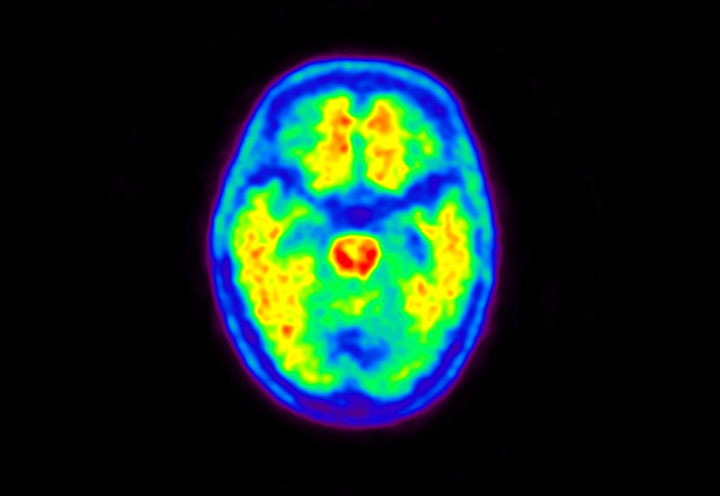

Head / Case5 : Amyloid

Courtesy : Kindai University Hospital

- Imaging protocol

- Injected dose: 4.27 MBq/kg, 18F-Flutemetamol

- Uptake time: 99 minutes

- Scan time: 20 minutes